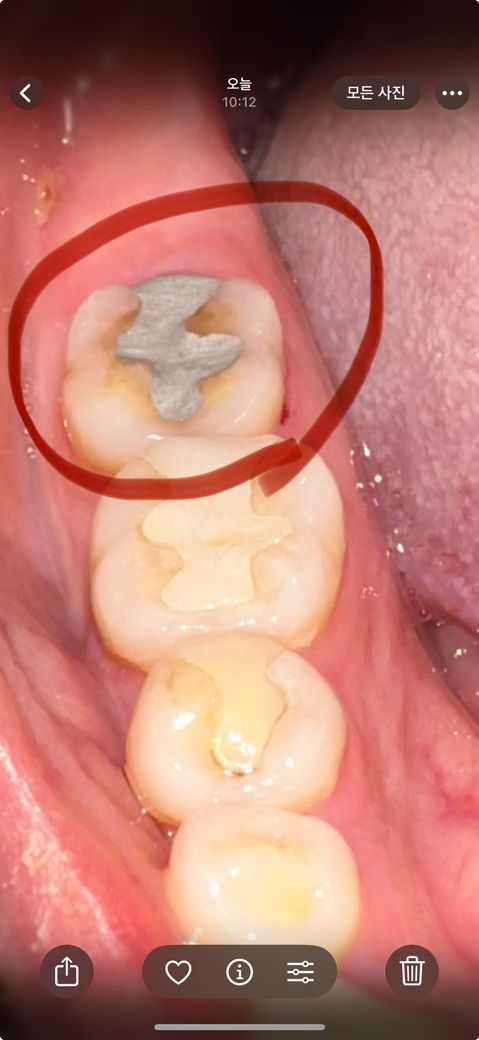

아말감으로 떼웠는데 질문 드려요 ㅠㅠ 전문가분들 도와주세요

어금니 금으로 일부분 떼운게 떨어져 기존에 치료 받았던 치과가 다른 지역이라 못가게 되어서 다른 치과에서 진료 받았는데 안맞아서 기존에 금을 못쓰게 되어서 아말감으로 떼워주셨습니다 요즘은 잘 안쓴다고 하던데 옛날 치과다 보니 보험 적용 되는걸로 해주셨어요 어제 낮에 떼웠는데 씹을때마다 시린 통증이 심합니다.. 이빨을 긁어내서 그런걸까요? 긁어내서 그런거라면 이 통증은 서서히 괜찮아지는건가요..? 가만 있으면 안아픕니다..

• 1번 째 사진